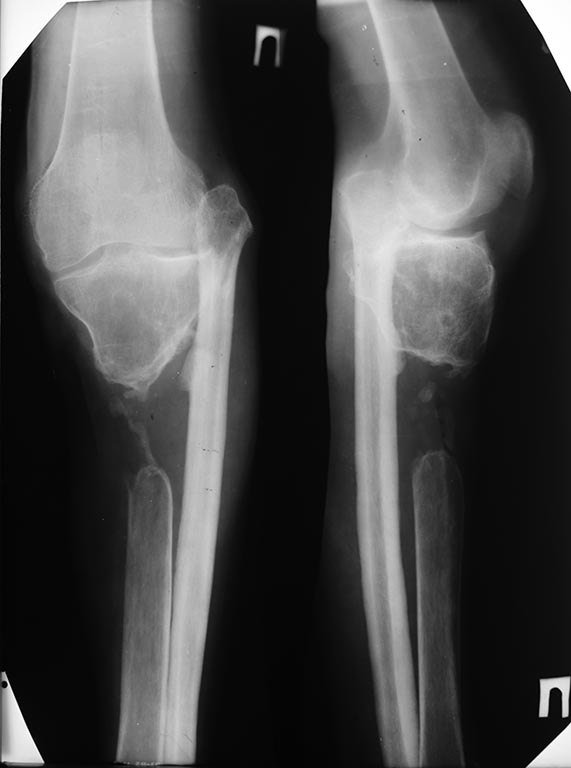

Коллеги, случайно наткнулся на рентгенограмму в архиве моего учителя.

Травма времен Великой Отечественной войны, огнестрельный перелом, дефект

большеберцовой кости.

Рентгенограмма 1985 года. В это время пациент передвигался с тростью с

практически полной нагрузкой на ногу. Малоберцовая перестроилась под

нагрузкой. Проксимальное межберцовое сочленение просело. Движения в

"коленном суставе" до 10 градусов.